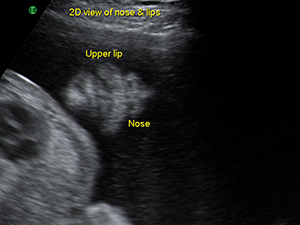

Fetal nose and lips in the second trimester Spine